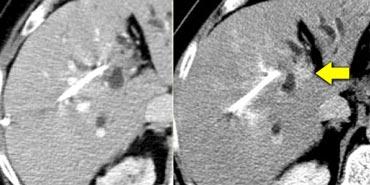

Tầm quan trọng của chụp cắt lớp không tiêm thuốc cản quang được minh họa qua trường hợp bên trái.

Trong thì động mạch, chúng ta thấy một cấu trúc tăng tỷ trọng ở phân thùy bên của thùy gan trái.

Hình ảnh này trông giống như một nốt ngấm thuốc rất gợi ý ung thư biểu mô tế bào gan giai đoạn sớm.

Tuy nhiên, nếu nhìn vào ảnh CCLVT không tiêm thuốc bên phải, chúng ta sẽ nhận thấy rằng đây không phải là hình ảnh ngấm thuốc. Đây chỉ là một nốt chứa sắt (nốt siderot) có tỷ trọng cao.

Chúng rất phổ biến và được ghi nhận ở tới 50% bệnh nhân xơ gan.